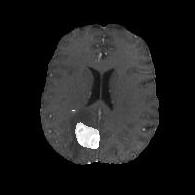

We argue that the sub-optimal paradigm of processing different abstractions within a single CNN pipeline can be remedied through the effective processing of information in a structured manner. Consequently, we devise strategies for disentangling the edge and texture information within a single training pipeline. Figure 2 illustrates how our proposed module, dubbed EG-CNN, can be paired with any existing CNN encoder-decoder to improve segmentation quality near intensity edges. We have applied our EG-CNN to the tasks of brain and liver tumor segmentation in medical images (Figure 3).

(1) Brain MR (2) Liver MR (3) Liver CT (4) Lung CT